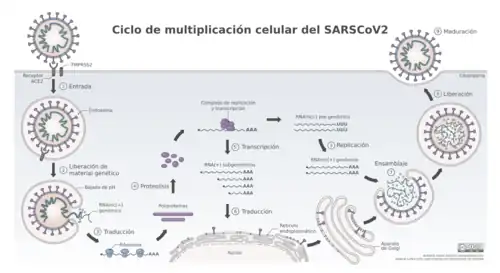

El ARN del virus SARS-CoV-2 codifica 4 proteínas estructurales: la proteína S (spike protein), la proteína E (envelope), la proteína M (membrane) y la proteína N (nucleocapsid). La proteína N está en el interior del virión asociada al RNA viral, y las otras cuatro proteínas están asociadas a la envoltura viral. La proteína S se ensambla en homotrímeros, y forma estructuras que sobresalen de la envoltura del virus. La proteína S contienen el dominio de unión al receptor celular y por lo tanto es la proteína determinante del tropismo del virus y además es la proteína que tiene la actividad de fusión de la membrana viral con la celular y de esta manera permite liberar el genoma viral en el interior de la célula que va a infectar.[97]

El SARS-CoV-2 penetra en la célula empleando como receptor a la enzima convertidora de angiotensina 2 (ACE-2 por sus siglas en inglés), una exopeptidasa de membrana presente fundamentalmente en el riñón, los pulmones y el corazón.[98] Se ha observado que los casos graves de COVID-19 presentan niveles de Angiotensina II muy altos. Y el nivel de angiotensina II se ha correlacionado con la carga viral de SARS-CoV-2 y el daño pulmonar. Este desequilibrio del sistema renina-angiotensina-aldosterona podría estar en relación con la inhibición de la enzima convertidora de angiotensina-2 por parte del virus. Este mismo mecanismo fue observado en el brote producido por síndrome respiratorio agudo grave en 2003.[97]

La glicoproteína S de la envoltura del virus interacciona con el receptor celular ECA2 (enzima convertidora de angiotensina 2), una proteína de la membrana celular que cataliza la conversión de angiotensia I en el nonapéptido angiotensina 1-9 o de angiotensia II en angiotensina 1-7. El virus entra por endocitosis. Una vez en el endosoma ocurre una bajada de pH mediada por lisosomas, que promueve la fusión de la membrana del endosoma con la envoltura del virus, lo que libera la nucleocápside al citoplasma. Proteasas celulares degradan la cápside y el genoma del virus queda libre en el citoplasma. A continuación, al ser un genoma ARN sentido positivo, la maquinaria celular traduce directamente a poliproteínas que son procesadas y se forma el complejo de replicación y transcripción. Luego se sintetiza la hebra complementaria de ARN pre-genómico sentido negativo que servirá como molde para replicar el genoma viral sentido positivo. Además, el complejo de replicación y transcripción sintetizará a una serie de ARN subgenómicos sentido positivo, más pequeños. Estos son los que se traducirán a las proteínas virales. Todo este proceso ocurrirá en el citoplasma de la célula. Se irán sintetizando las proteínas estructurales que se expresarán en la membrana del retículo endoplasmático. Ahí, en el retículo, es donde ocurrirá el ensamblaje. De hecho la envoltura del virus proviene de la membrana del retículo endoplasmático. La partícula viral viajará, a través del sistema de transporte de vesículas celular en el que interviene el aparato de Golgi, hasta la superficie. La partícula viral saldrá de la célula por exocitosis. Tras una última fase de maduración, en la que intervienen proteasas virales, todos los componentes del virus encajarán, la partícula será infecciosa y podrá comenzar un nuevo ciclo celular.[99]